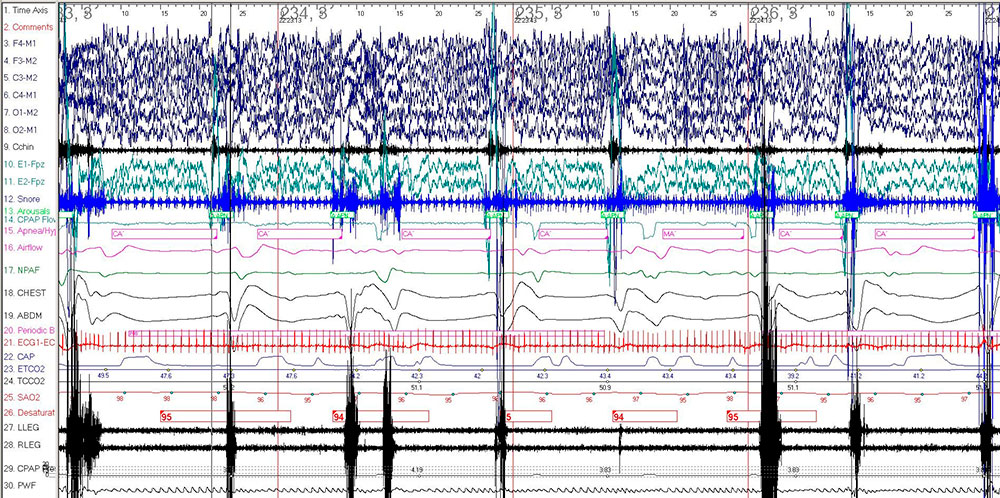

Figure 2: 2-minute epoch on BPAP 8/4 cm H2O. Electroencephalogram leads (F4-M1, F3-M2, C3-M2, C4-M1, O1-M2, O2-M1); Electromyogram leads (Cchin, LLEG, RLEG), Ocular leads (E1-M2, E2-M1), Respiratory sensors (NPAF, Airflow), EKG leads (ECG1, ECG2), CAP (capnography), SAO2 (oxyhemoglobin saturation), PWF (pulse wave form).

Figure 2 depicts central apneas on positive airway pressure. The development of central apnea in OSA patients during administration of PAP has been described in adults and referred to as treatment-emergent central sleep apnea or complex sleep apnea.